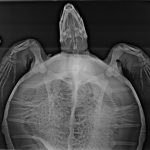

Severe left and right front flipper entanglement, severe neck entanglement including an opening on the ventral side of the neck, caudal left side of carapace is concave and misshapen. Fishing line was monofilament. FP score 1/3, few small body tumors, right eye appears to have two small eye tumors developing. Took 3-view radiographs appears to have moderate-severe pneumonia.

This animal is in critical condition.